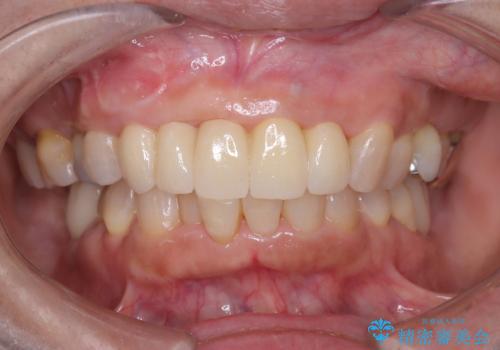

前歯の隙間とへこみが舌で触ると気になる|矯正治療は絶対にしたくない|抜歯即時インプラント+オールセラミッククラウンで審美修復

[ セラミック治療 ] 前歯の見た目を改善したい